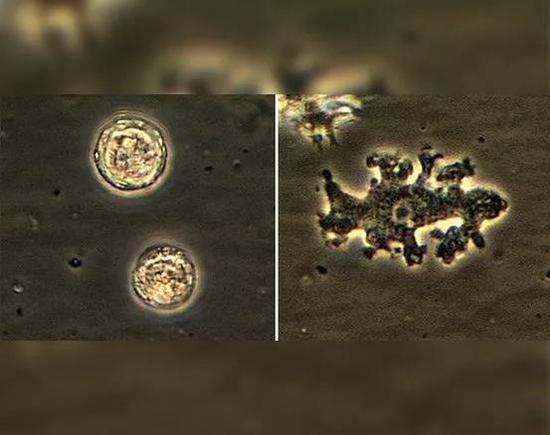

洗鼻不当引起“食脑虫”感染

西雅图的一名妇女患上了罕见且致命的“食脑”阿米巴原虫感染,或由于不正确使用洗鼻器所致。据悉,这位69岁的妇女一直在用洗鼻器冲洗鼻子,但用的溶液却不是推荐使用的无菌水或盐水溶液。不久,她鼻子上长了一个小疹子,且不会消失。一年后,该女子突发癫痫。

起初,医生认为她患有脑瘤,但测试显示她感染了一种叫做阿米巴(Balamuthia mandrillaris)的变形虫。这类感染非常罕见,自1993年以来,美国仅报告了约70例。医生怀疑这名妇女是经未消毒的自来水中感染的。

该病例发表在12月号的《International Journal of Infectious Diseases》杂志上。